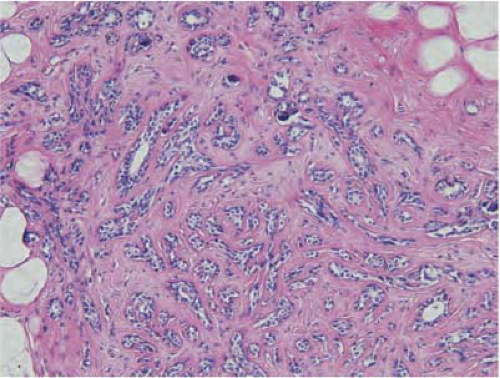

On physical examination, phyllodes tumor can be indistinguishable from fibroadenoma. A large breast mass >3 cm with rapid growth should prompt suspicion

for phyllodes tumor and requires core needle biopsy or surgical excision. Microscopically, they have characteristic hypercellular stroma around the ductal elements, which form a leaf-like pattern giving the lesion its name (Fig. 21-7). A high mitotic count, nuclear pleomorphism, infiltrative tumor margins, and stromal overgrowth are the main criteria used to assess biologic behavior. Benign tumors are characterized by increased cellularity, lack of stromal overgrowth, mild to moderate cellular atypia, circumscribed margins, and low mitotic rate (<4 per 10 high power fields). Borderline tumors are characterized by higher degree of cellularity and atypia, mitotic rate of 4 to 9 mitoses per 10 high power fields, and microscopic infiltrative borders. Malignant tumors have marked stromal cellularity, atypia, infiltrative margins, stromal overgrowth, and more than 10 mitoses/10 high power fields (36,37).

![]() FIGURE 21-7 Phyllodes tumor, benign. The tumor has a frond-like architecture, with compressed ducts lined by ductal and myoepithelial cells. |